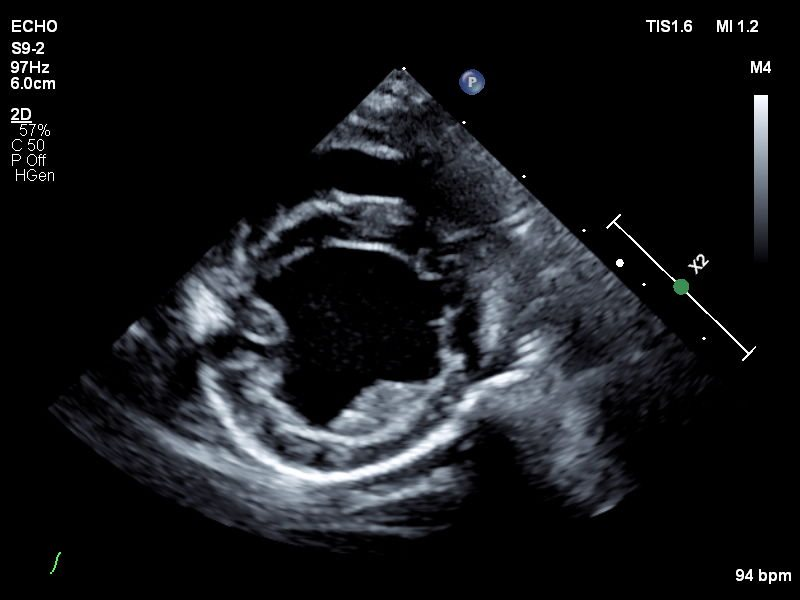

Echocardiograms

Veterinary echocardiography is a type of ultrasound imaging that focuses on the heart. Echocardiography assesses the structure and function of an animal's heart. This non-invasive procedure employs ultrasound technology to produce detailed, real-time images of the heart's chambers, valves, and blood flow. Echocardiography is essential for diagnosing and monitoring heart conditions such as heart murmurs, cardiomyopathy, and valve disorders. It helps veterinarians evaluate the severity of heart disease, guide treatment decisions, and monitor the effectiveness of therapies, all while ensuring the animal's comfort and safety.